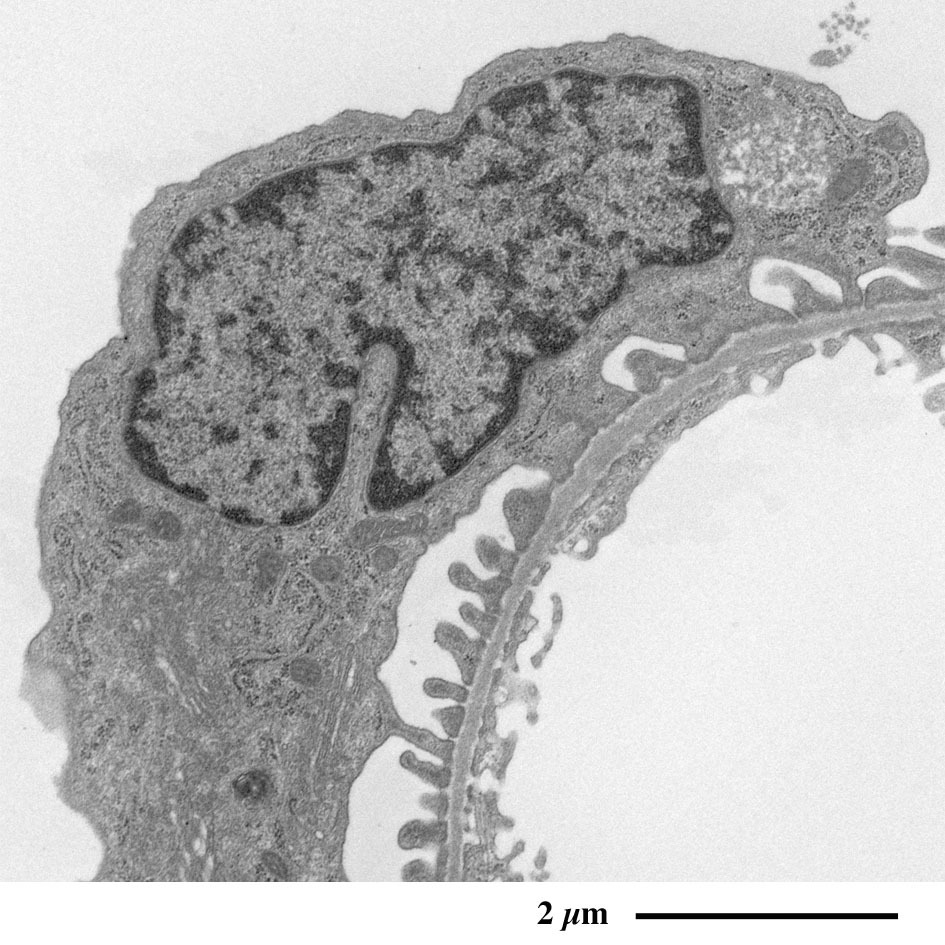

肾小球放大图像

可观察到足突在毛细血管外周包绕的形态。

可观察到足细胞(黄色)突起包绕在毛细血管(红色)的外周。

绿色:肾小囊腔、蓝色:血管内皮细胞